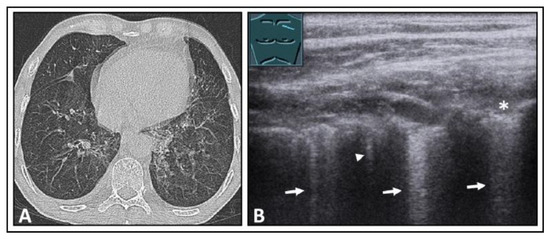

6. Interstitial Lung Disease